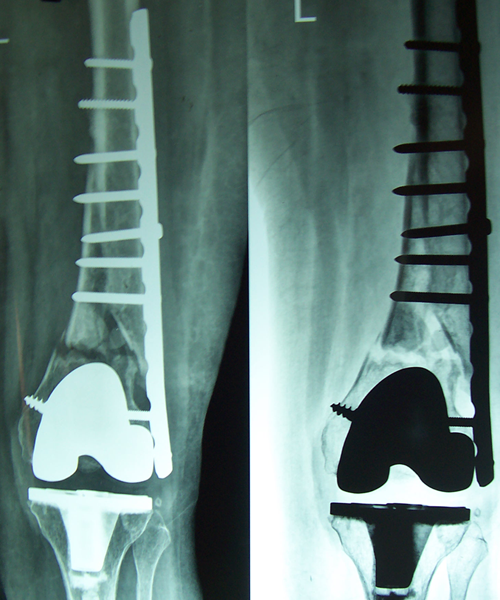

Case:14 Periprosthetic Fracture

60 years old patient with total knee replacement on left knee presented with open grade 1 injury. Debridement & slab given on emergency bases. Fixation with plate & screws done. Union was seen after 6 months.

Pre-Op AP

Pre-Op Lat.

Immdiate Post-op

1 and half months Post-op

2 and half months Post-op

3 and half months Post-op

4 and half months Lateral

6 Years Follow-Up